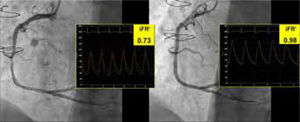

Se presenta el caso de un varón de 59 años, fumador, con antecedentes de hipertensión, diabetes y lesión de 2 vasos (arteria descendente anterior izquierda y arteria circunfleja) tratada con un injerto coronario en 2012. El paciente fue remitido a nuestro hospital con un infarto de miocardio sin elevación del segmento ST. La angiografía reveló unos injertos permeables y una luz con múltiples giros en el segmento medio de la arteria coronaria derecha (), lo cual se confirmó en la tomografía de coherencia óptica (figura 1, ). Un índice diastólico instantáneo sin ondas (iFR) de 0,73, que indica deterioro del flujo (figura 2) motivó el implante de un stent farmacoactivo, con buenos resultados (). El iFR tras el implante del stent fue de 0,98.

La evaluación fisiológica de la lesión resulta útil para el pronóstico en la revascularización percutánea, y tanto la guía europea como la estadounidense recomiendan esta práctica. Anteriormente se proponía un tratamiento conservador para la enfermedad de la arteria coronaria en entramado, pero en nuestro caso se muestra por primera vez un deterioro del flujo inducido por los microconductos en entramado. Nuestras observaciones contribuyen a mejorar el conocimiento de esta anomalía, con importantes consecuencias para el tratamiento. Esta figura se muestra a todo color solo en la versión electrónica del artículo.